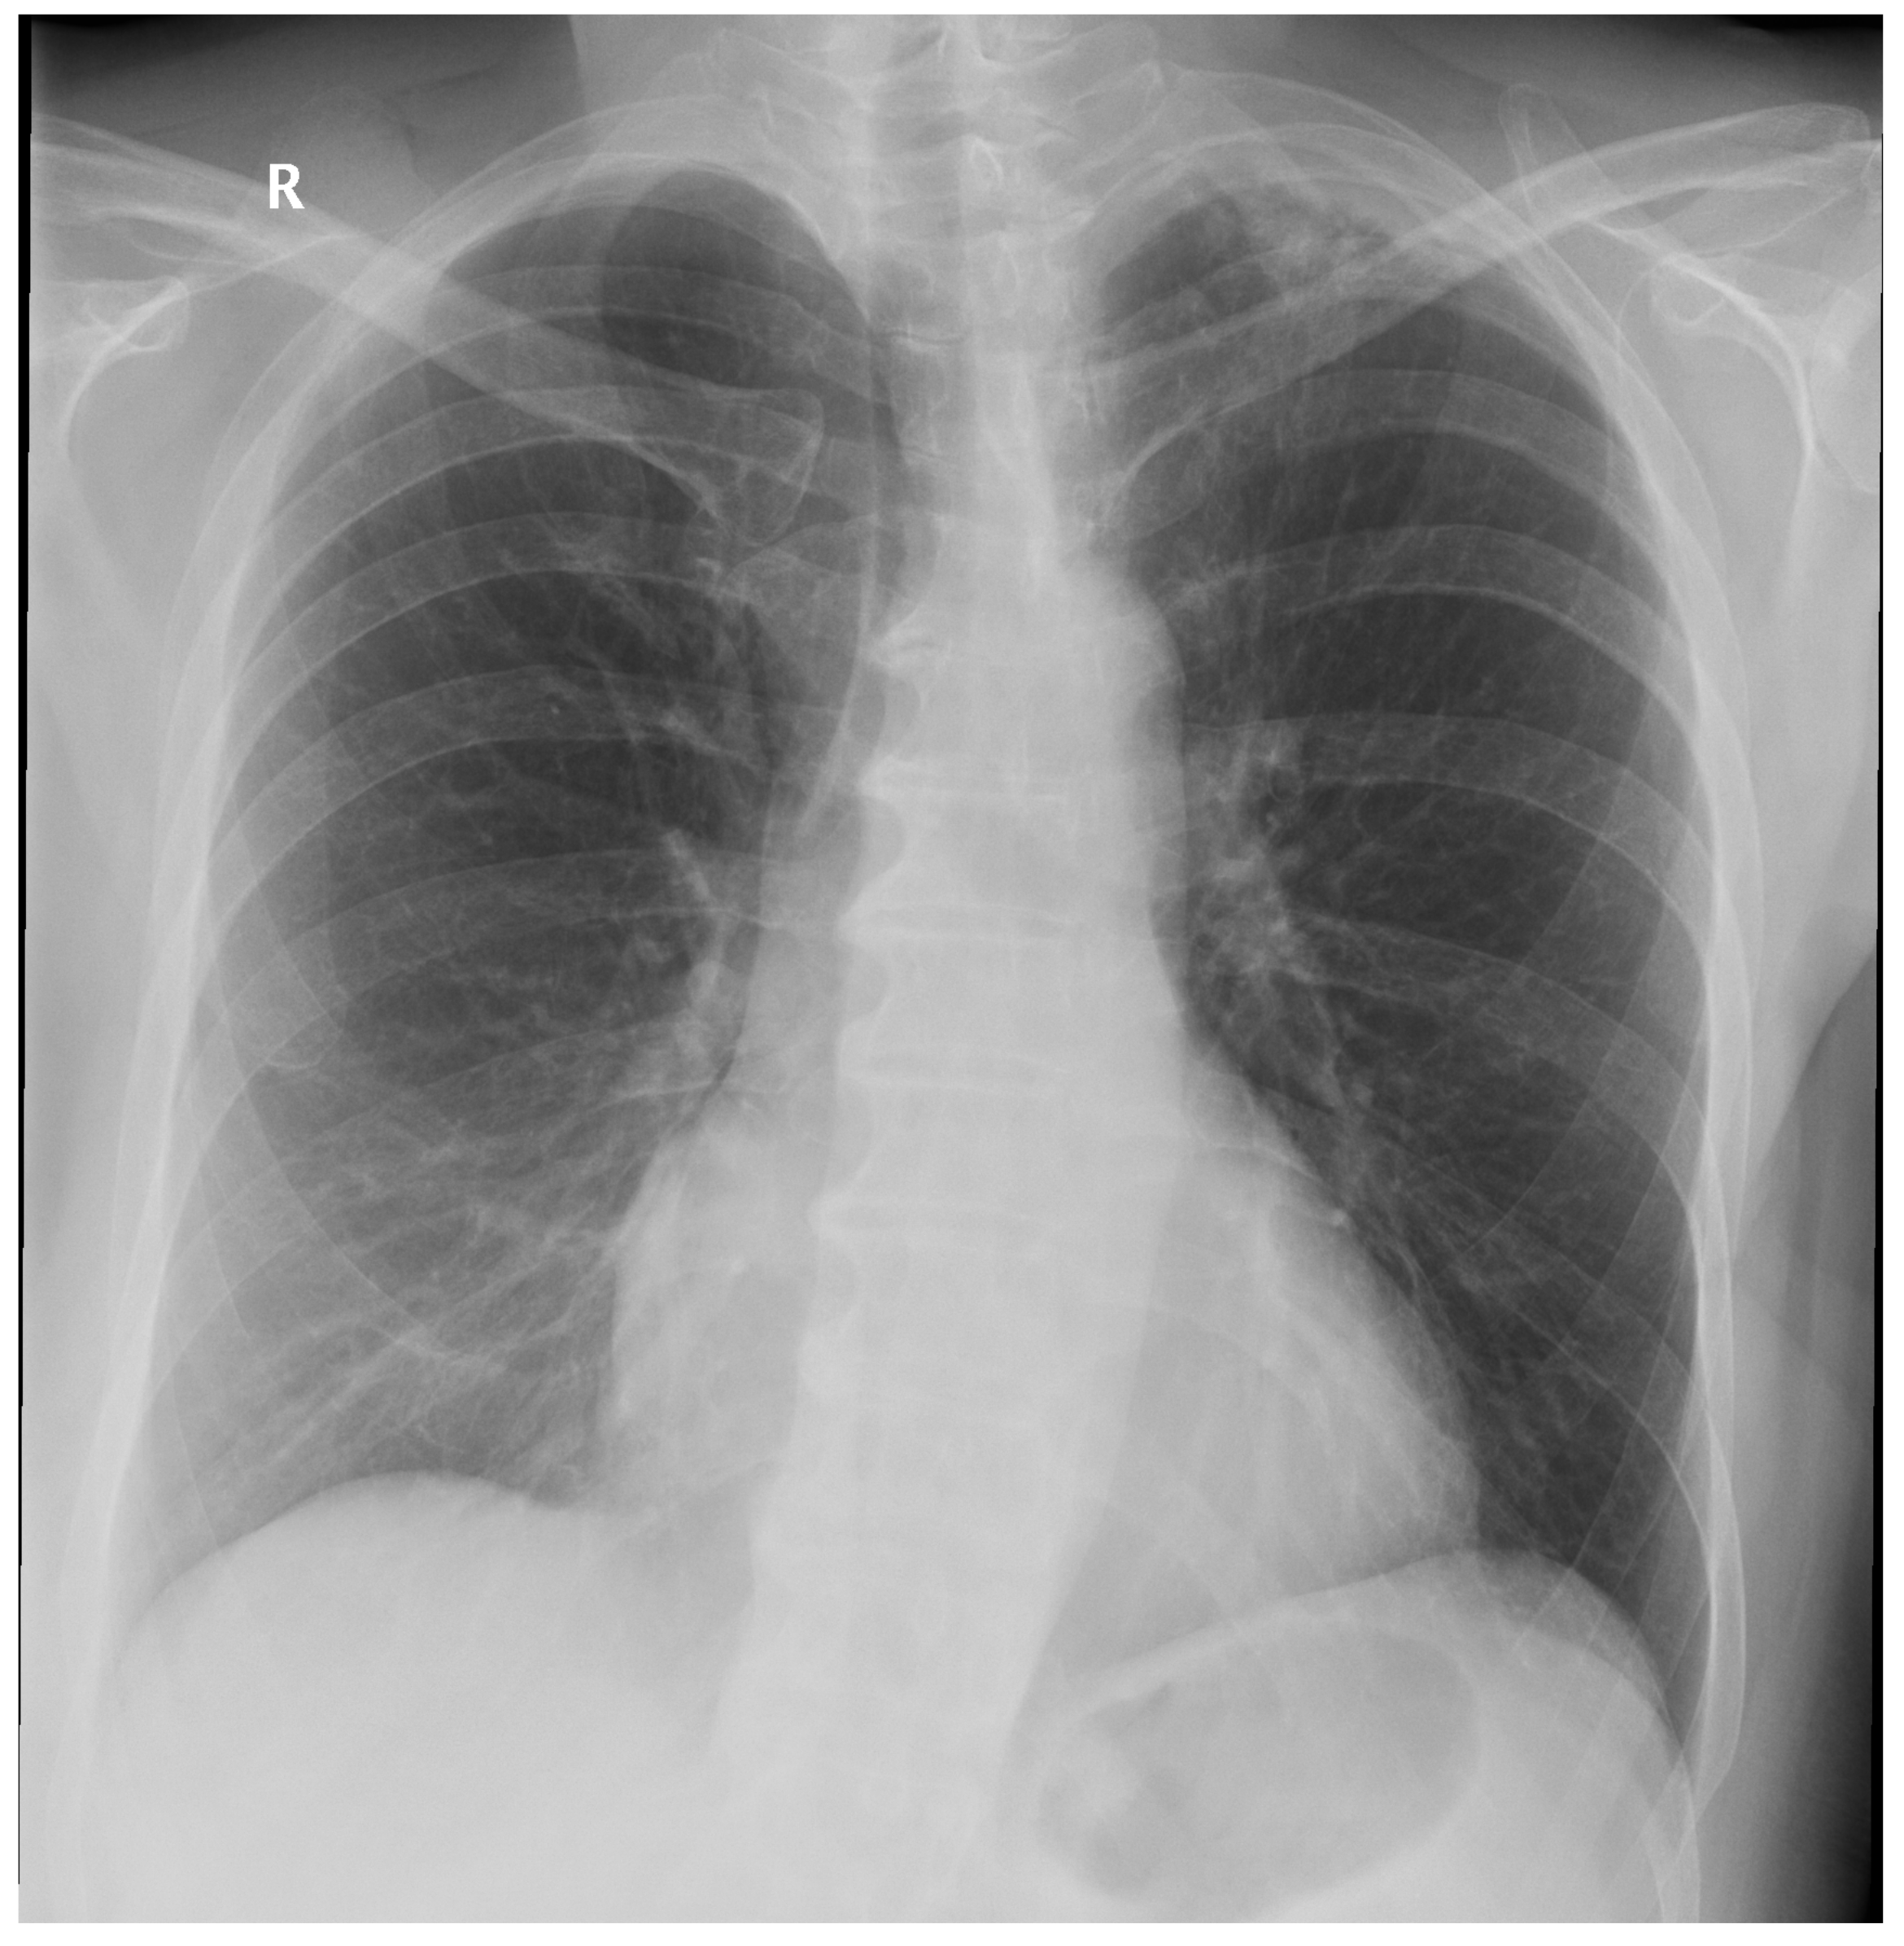

A total of 127 images with established ground truth were evaluated: 40 (31.5%) with a finding and 87 (68.5%) without any finding. The DLAD correctly identified 37 images as abnormal and 56 images as normal (73.2% in total). A total of 31 (24.4%) normal images were incorrectly classified as abnormal. The higher false positive rate was expected since DLAD was trained to assign even suspect findings as abnormal. Another three (2.4%, Figure A2, Figure A3, Figure A4) images were incorrectly classified as without any finding, even though they were with findings (false negative rate) (Table 3).

Figure A2.

False Negative image #1 incorrectly classified by DLAD software during the retrospective study. The software failed to detect a lesion in lung parenchyma. Assessed radiologists #5f0 and #24a also incorrectly classified this image as Normal.